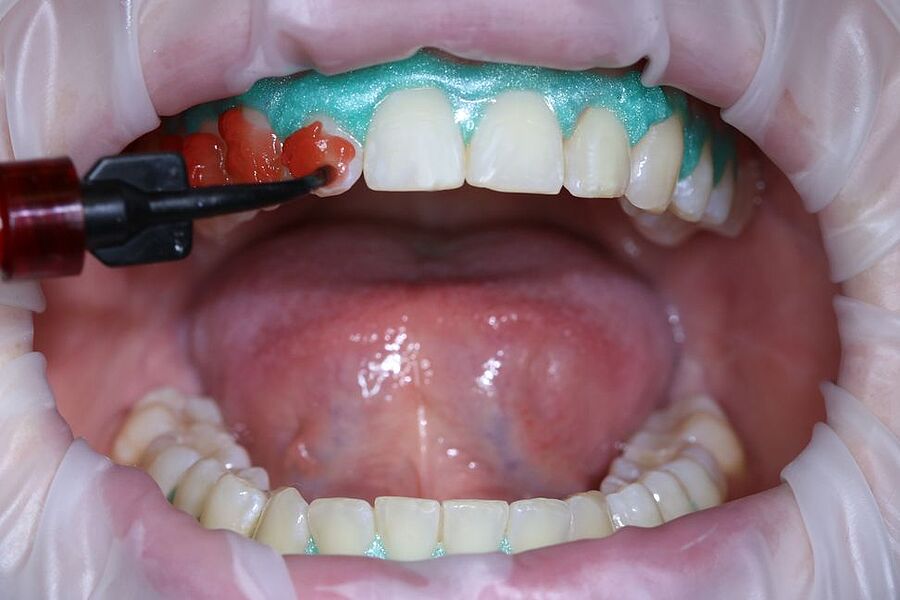

In der Ausgabe 02/2023 der Fachzeitschrift Zahnmedizin up2date berichten unsere beiden Ästhetik-Spezialisten wie ein professionelles In-Office-Bleaching vitaler Zähne funktionieren kann. Die hierzu nötigen Arbeitsschritte einschließlich der klinischen Voraussetzungen werden Schritt für Schritt anhand eines Bildessays illustriert.

Zeitschrift: Zahnmedizin up2date

Ausgabe: 02/2023

Autoren: Dr. Helena Schmidt-Park,

Dr. Dr. Hans Ulrich Brauer, M.A., M.Sc.